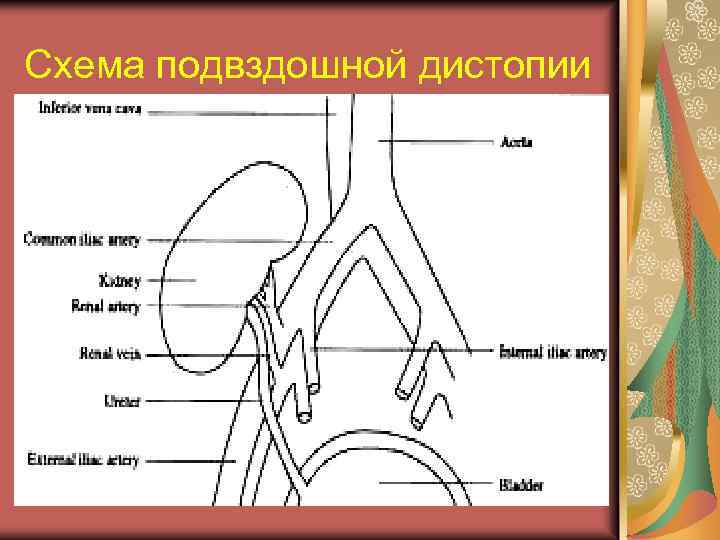

Подвздошная дистопия Почка располагается в подвздошной ямке Нижний полюс почки - на уровне входа в малый таз Лоханка отходит от передней поверхности и ориентирована латерально Короткий мочеточник Сосуды отходят от аорты вблизи бифуркации или подвздошных артерий Лучше визуализируется через наполненный мочевой пузырь

Схема подвздошной дистопии